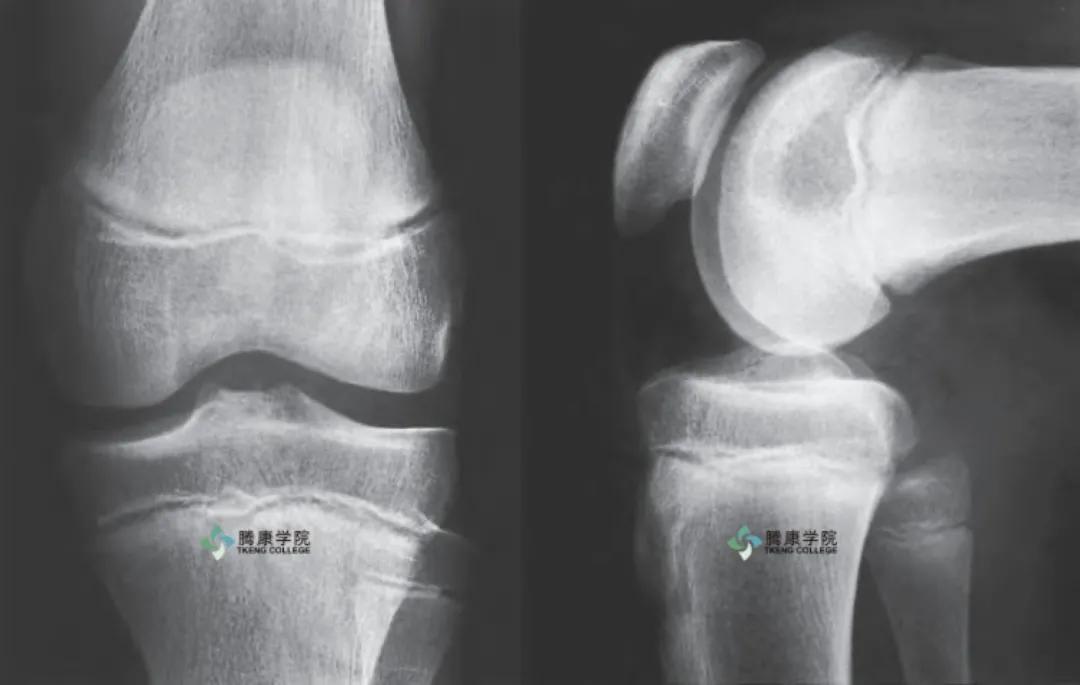

胫股关节

胫股关节是一个复杂的滑膜关节,为膝关节的组成部分。胫骨近端关节面(胫骨平台))相对胫骨干长轴向后下倾斜。胫骨后倾程度在出生时最大,随年龄增大而减少,习惯下蹲姿势的人后倾较明显。

胫骨平台内、外侧面与相对应的股骨髁相关节。在关节面后部的远端有一粗糙的、水平方向的凹槽,有关节囊和内侧副韧带后部附着。胫骨内侧髁的前内侧面粗糙,借一不明显的骨嵴与胫骨干内侧面隔开。

胫骨髁关节面之间的区域粗糙而狭窄,有髁间隆起,其边缘向近端突起,形成内、外侧髁间结节。髁间区的前、后部随关节面的分开均增宽。髁间前区的前部最宽。在前内侧,内侧关节面的前方有一凹陷,内侧半月板前角附着于此。

股骨关节面覆有关节软骨的股骨髁几乎呈凸面。半月板提高了胫股关节的匹配度,半月板呈凹面与股骨相适应,外侧胫骨--半月板关节面较深。

半月板撕裂是膝关节最常见的损伤,在运动员和一般人中发生的相对频繁。基本上,半月板撕裂通常与股骨髁有力的轴向扭转有关。受压膝关节内的轴向扭转可以对半月板进行挤压,并使其移位。移位或折叠的半月板会在力学上阻碍膝关节的运动。

内侧半月板受损伤的概率是外侧半月板的两倍。内侧半月板撕裂的损伤机制通常涉及绕轴旋转,也可能会涉及施加在膝关节外侧的外力。该力通常被描述为“外翻力”, 它可以导致膝关节的外翻位置,以及随后被施加在内侧副韧带与后内侧囊上的很大应力。由于内侧半月板与这些结缔组织之间的解剖*联学**系,传递至膝关节的巨大外翻力可以间接限制并进而损伤内侧半月板。

如果膝关节存在异常对位或有韧带不稳定病史,半月板撕裂的风险会加大,这种情况在前交叉韧带最为明显。

前交叉韧带是膝关节最常发生完全断裂的韧带。大约1 / 2 的前交叉韧带损伤发生在15~25 岁的人之中, 经常在高速体育活动中发生。如美式足球、高山滑雪、长曲棍球、篮球和橄榄球。大多数前交叉韧带撕裂涉及膝关节的片刻半脱位. 导致对其他组织的次要创伤,包括骨骼、关节软骨、半月板或内侧副韧带。

前交叉韧带的损伤可导致膝关节的严重不稳定与可能的应力运动学。存在前交叉韧带缺陷的膝关节还容易导致其他结构的损伤或退化。

后交叉韧带损伤与高能量的创伤有关.如汽车事故或进行如美式橄榄球等身体接触运动。涉及后交叉韧带损伤的运动损伤的比例通常为2 % ~10 % 。大约1 / 2 的后交叉韧带损伤和膝关节其他组织的受伤( 包括半月板、前交叉韧带与后外侧艇)同时发生。